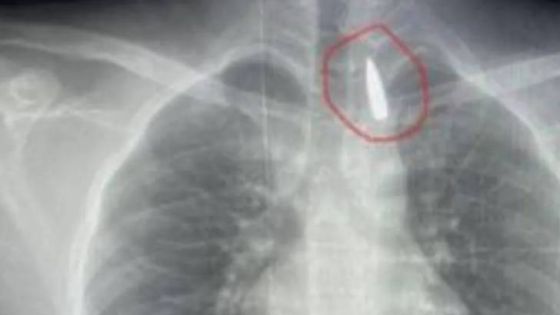

وتمثلت العملية، التي وصفت بـ”بالغة الخطورة”، في استخراج مقذوف ناري كان قد استقر في القفص الصدري على مقربة شديدة من الشريان الأورطي.

وأشار إلى أن المريض، وهو أحد المصابين القادمين من قطاع غزة، كان قد تعرض لإصابة بطلق ناري منذ فترة، استقر المقذوف على إثرها داخل تجويف القفص الصدري.

وأكد “عبد الله” أن خطورة الحالة تكمن في موقع المقذوف، حيث كان مستقرا “قرب الشريان الأورطي”، وهو، كما أوضح البيان، “أكبر وأهم شرايين الجسم والمسؤول عن تغذية جميع الأعضاء الحيوية”.